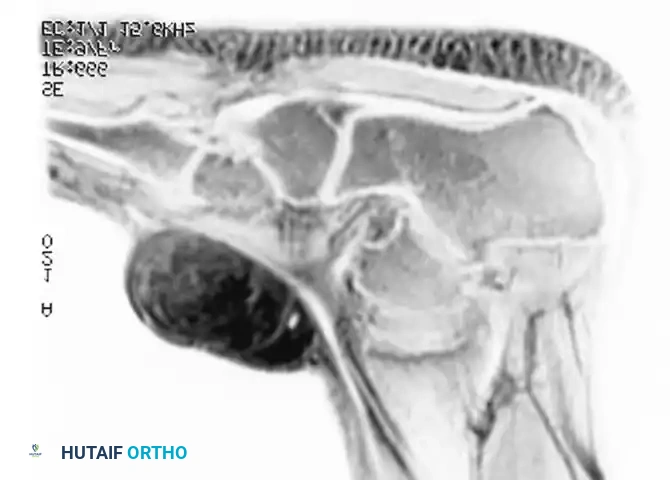

Imaging:

Conventional radiographs may demonstrate a non-specific soft-tissue density but are usually normal. MRI reveals a well-circumscribed mass that is typically isointense to muscle on T1-weighted images and hyperintense on T2-weighted images. Central necrosis is a hallmark of larger, high-grade tumors.

Axial MRI showing a large soft-tissue mass in the thigh with mixed signal intensity, characteristic of UPS/MFH.

Coronal MRI demonstrating the proximal-distal extent of the tumor within the muscular compartment.